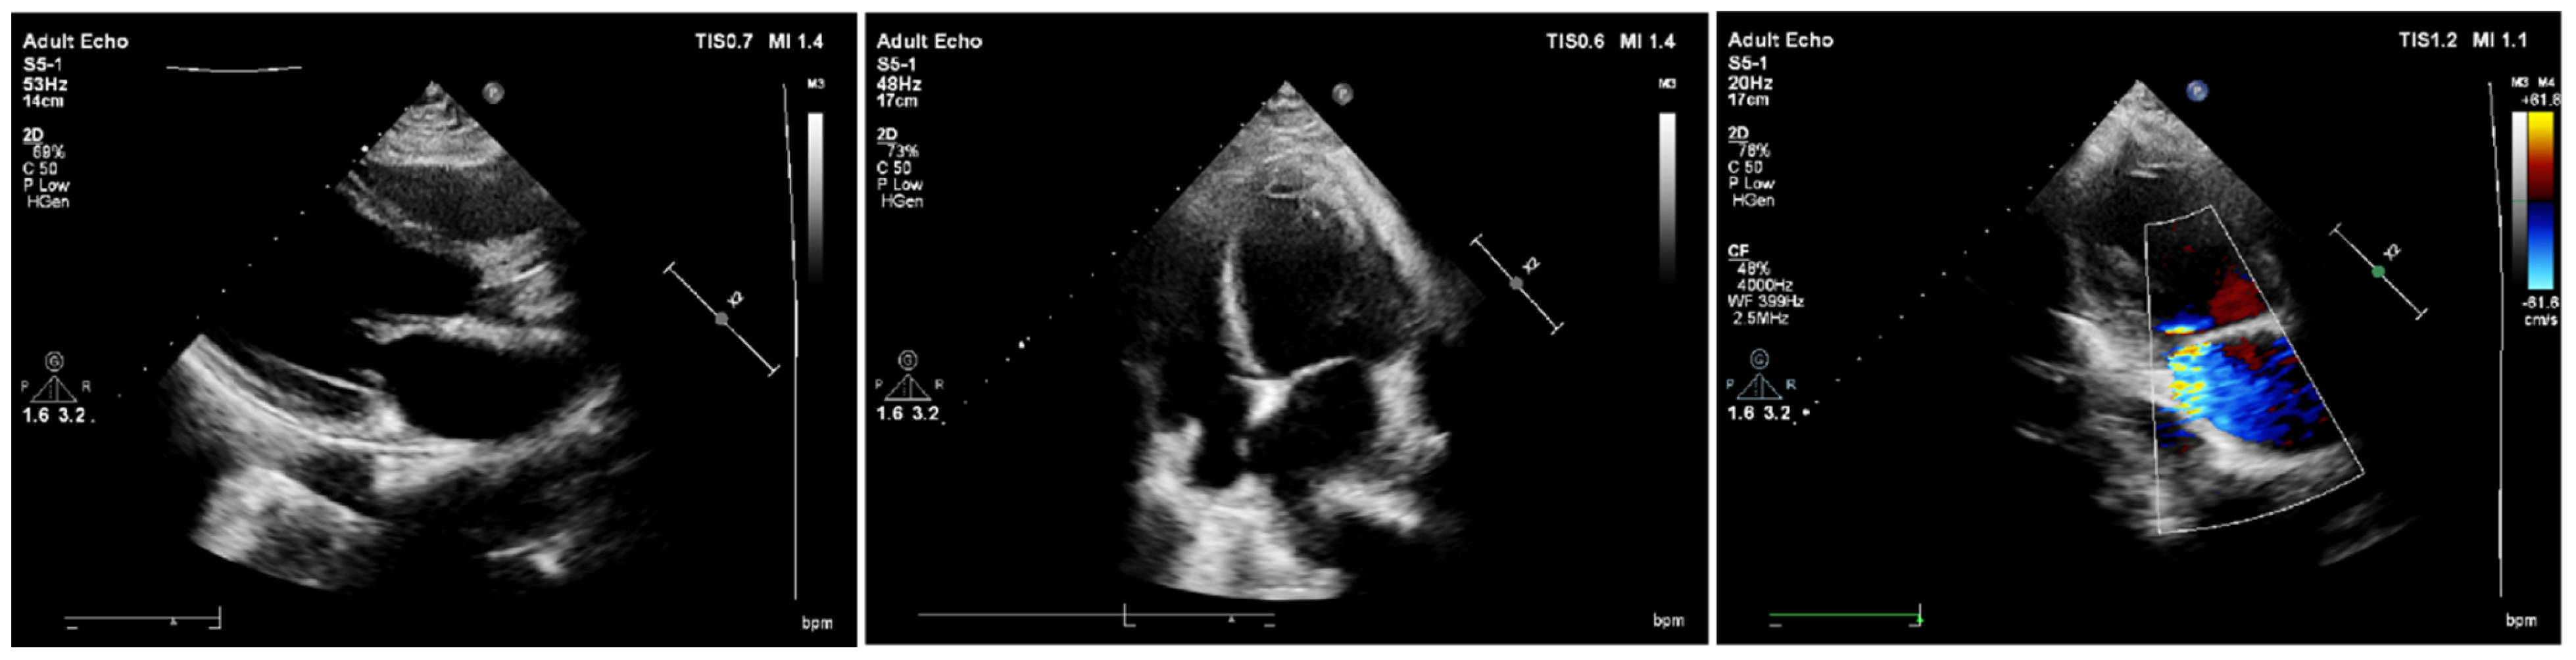

2. Case Report